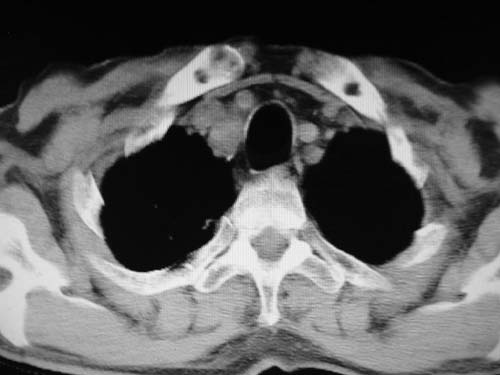

男,80岁

左下肺静脉扩张,原因?建议cta

左肺动脉异常增粗,建议增强。

肺动脉瘤。建议先行ct增强扫描

左肺动脉异常增粗,考虑肺动脉狭窄可能。

左肺动脉异常增粗,建议ct增强,排除肺门肿瘤

1)考虑左肺动脉瘤可能性大,建议增强。2)右肺上叶继发性肺结核。3)右侧胸膜增厚、钙化,左侧胸膜反应。

肺动脉段突出,左右肺门不等大,左肺门明显增大,肺动脉干及左肺动脉明显增宽,考虑先天性肺动脉狭窄瓣膜狭窄型。

)考虑肺动脉扩张,右心室增大,主动脉弓段正常位弓后段明显变小(不会是动脉导客未闭吧,不知患者有何症状病史)0。2)右肺上叶继发性肺结核。3)右侧胸膜增厚、钙化,左侧胸膜反应。

肺动脉高压,左肺动脉瘤样扩张。